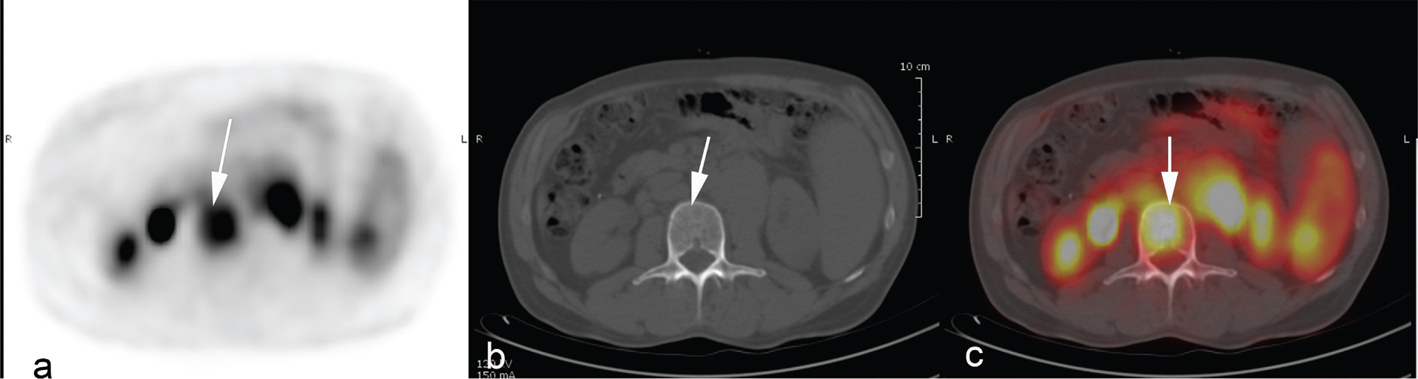

The greatest advantage of PET/CT in lymphoma is that it can accurately separate residual, viable lymphoma from scar tissue, which is often present after therapy (23). The ability to early identify tumor response before tumor shrinkage makes PET/CT as useful tool for early treatment evaluation. Early metabolic response by PET/CT after few cycles of chemotherapy was shown to be highly prognostic for progression-free survival (PFS), with PET-positive patients after two cycles of ABVD having 2-year PFS of 0% versus 96% for those who were PET-negative at the same time point (Figures 2 and 3) (24). This was subsequently confirmed in a larger international series (25). These observations spurred interest in using PET/CT to guide treatment based on early response in both escalation and de-escalation trials (4, 26, 27). These clinical trials have paved the way for more personalized treatment strategies in HL and are described in detail in the sections about management of early- and late-stage HL.

Fig 2

Figure 2. A young woman with a history of progressive swellings, dyspnea, and fever. Biopsy revealed Hodgkin lymphoma. Abnormal FDG-uptake at baseline PET/CT (a,b,c) was confined to enlarged clavicular and mediastinal lymph nodes, i.e., disease stage 2. Interim PET/CT (d,e,f) after two cycles of ABVD (doxorubicin, bleomycin, vinblastine, and dacarbazine) was coherent with complete metabolic response (Deauville Score 2) although lymph nodes remained enlarged on CT scan.

Fig 3

Figure 3. A young woman with Hodgkin lymphoma, stage II. Baseline FDG PET/CT (a). Interim PET/CT (b) performed after two cycles of ABVD (doxorubicin, bleomycin, vinblastine, and dacarbazine,) revealed partial metabolic response with residual FDG-uptake above liver uptake (lymphoma SUVmax=8.6, liver SUVmax=2), classified as DS 4.

A common language for assessing metabolic response by PET/CT is necessary to ensure that the treatment decisions are reproducible. The international harmonization criteria from 2007 proposed a dichotomous scoring system where mediastinal blood pool activity was recommended as the reference background activity to define PET positivity for a residual mass greater or equal to 2 cm in greatest transverse diameter, whereas background update was to be used for assessment of smaller lesions (28). However, dichotomous scores in lymphoma proved suboptimal. Response-adapted treatment strategies based on interim PET/CT should enable tailoring the risk of false positive/false negative assessments to the question being asked in the trial, which can be done using more granular response reporting (29). The Deauville 5-point score (DS) is now the standard for reporting PET/CT response assessment in lymphoma (Figure 2 and 3) (7). DS was conceived to graduate the intensity of 18F-Fluoro-deoxy-glucose (FDG) uptake in previously identified lymphoma lesions relative to the liver uptake. DS 1 and 2 represent a FDG uptake lower than that of liver, uptake DS 3 represents an intensity of uptake up to that of liver, and DS 4 and 5 represent different degrees of FDG uptake above liver level and new lesions (score 5) (7). For interim and end-of-therapy response assessment in HL, a scores between 1 and 3 are conventionally considered as complete metabolic response (Figure 2) whereas DS 4 or 5 represent active HL (Figure 3) (7). Several studies have shown that the Deauville score is high prognostic in HL using DS 1–3 to define a complete metabolic response (CMR) and DS 4–5 as non-response. In two recently finalized trials of PET-guided de-escalation strategies (HD16 and D18) conducted by the German Hodgkin Study Group, the trials were designed to use DS 1–2 (above the mediastinum) as negative (or equivalent), but further analyses of these trials showed that residual uptake above liver level (DS 4–5) was better in predicting outcomes (3032). In the HD16, 5-year PFS was 93.2% among PET-2-negative patients and 88.4% in PET-2-positive patients (P = .047) when using DS3+ as definition of a positive PET/CT, but when using liver cutoff (DS 4+) for PET-2 positivity, 5-year PFS was 93.1% for PET negative patients vs 80.9% for PET positive patients (P = .0011) (30). In post-hoc analyses of HD18, DS4 was the only risk factor for inferior overall survival in a cohort of patients with DS 1–4 after two cycles of BEACOPP escalated after adjustments for other risk factors (32). The timing of interim PET/CT in HL is conventionally after two courses of chemotherapy, but a negative PET/CT after 1 cycle also has a very high negative predictive value (2-year PFS 98%) and is currently used in clinical trials of very early PET/CT adapted treatment strategies (NCT03517137) (33).